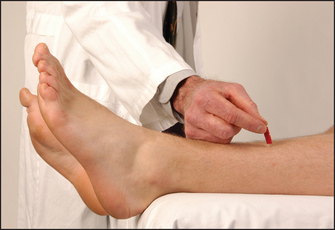

After telling the patient what is going to happen, use a blunt object (such as the key to an expensive car) to stroke up the lateral aspect of the sole and curve inwards before it reaches the toes, moving towards the middle metatarsophalangeal (MTP) joint (see Figure 34.41). The patient’s foot should be in the same position as for testing the ankle jerk. The normal response is flexion of the big toe at the MTP joint in patients over 1 year of age. The extensor (Babinskio)7 response is abnormal and is characterised by extension of the big toe at the MTP joint (the upgoing toe) and fanning of the other toes. This indicates an upper motor neurone (pyramidal) lesion, although the test’s reliability can be relatively poor. Bilateral upgoing toes may also be found after a generalised seizure, or in a patient in a coma.